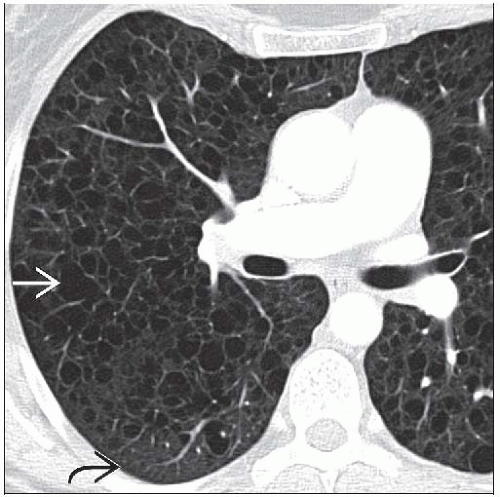

Lymphangioleiomyomatosis is a rare disease of the lungs. It is characterized by atypical proliferation of smooth muscle cells in the lungs. The consequences are dyspnea, cough, hemoptysis, pneumothorax, and death. Radiologically, the condition manifests as cyst and multifocal nodularities. Reference: https://www.ncbi.nlm.nih.gov/pmc/articles/PMC3337385/#:~:text=Lymphangiomyomatosis%20(LAM)%20is%20a%20rare Image via: https://radiologykey.com/lymphangioleiomyomatosis/